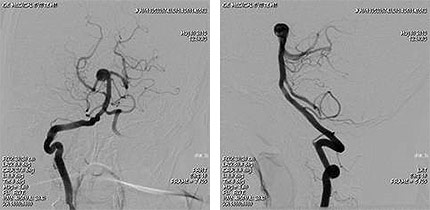

![]() |

| 脳血管撮影(DSA) |